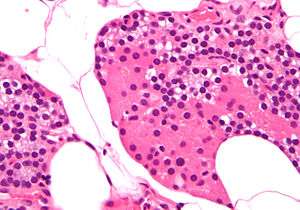

The parathyroid glands are named for their proximity to the thyroid — and serve a completely different role than the thyroid gland. The parathyroid glands are quite easily recognizable from the thyroid as they have densely packed cells, in contrast with the follicular structure of the thyroid.[7] Two unique types of cells are present in the parathyroid gland:

- Chief cells, which synthesize and release parathyroid hormone. These cells are small, and appear dark when loaded with parathyroid hormone, and clear when the hormone has been secreted, or in their resting state.[8]

- Oxyphil cells, which are lighter in appearance and increase in number with age,[8] have an unknown function.[9]

High magnification micrograph. H&E stain. The small, dark cells are chief cells, which are responsible for secreting parathyroid hormone.